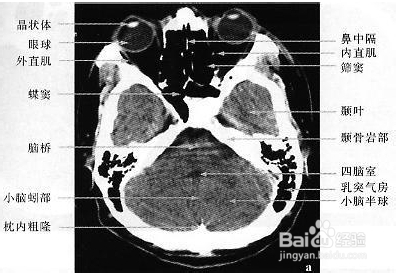

1、 (1)影像学检查包括

①头颅CT平扫;

②头颅磁共振成像(MRI )检查;

③脑血管造影;

④头颅磁共振血管造影(MRA );

⑤脑血流图。